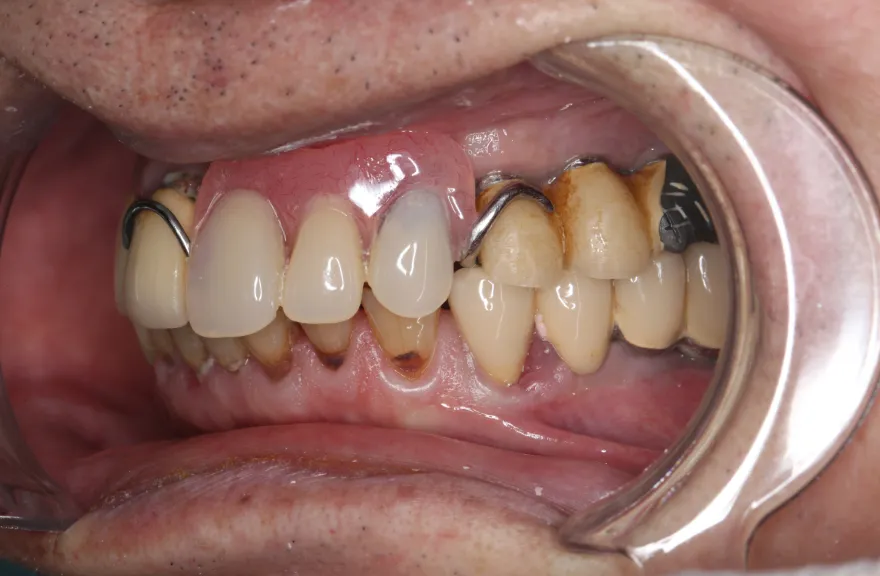

【治療例 3】奥歯が痛い、全体的にみて欲しい 60歳

- 相談内容

-

今まで何回歯を入れてもトラブルが起きるために、奥の歯を入れないまま今日に至る、ということでした。

噛み合わせ・骨格を読み解き、今後の人生でトラブルが起きにくいように全体的な治療計画を練りました。 - 治療費用・方針

骨格の前後的な差がある方でした。術前のレントゲンより、上下で歯牙の損傷に明らかな差があるのがみてとれます。

上の歯がないところにインプラント治療を行い、上顎は全てインプラントフィクスチャーによる固定性の歯を入れられることも費用的には可能な方でした。

しかし、治療において重要なのは今目の前の歯を見ることではなく、なぜ目の前の歯になったかを考え、未来へ活かすことです。

骨格的な前後差を考慮することなく歯をいれても、装着した人工物は決して長持ちしません。

今回の症例では、敢えて上顎は総義歯形態をとり、骨格的な前後の差を解消するよう工夫しました。

上顎の残っていた歯も、差し歯としては使えずとも、敢えて根だけ残すことによって組織を温存し、義歯の安定に寄与するよう設計しました。

ここまで全体的にしっかり治療しておけば、今後の人生においてトラブルになるようなことにはならないでしょう。 - 治療のリスク